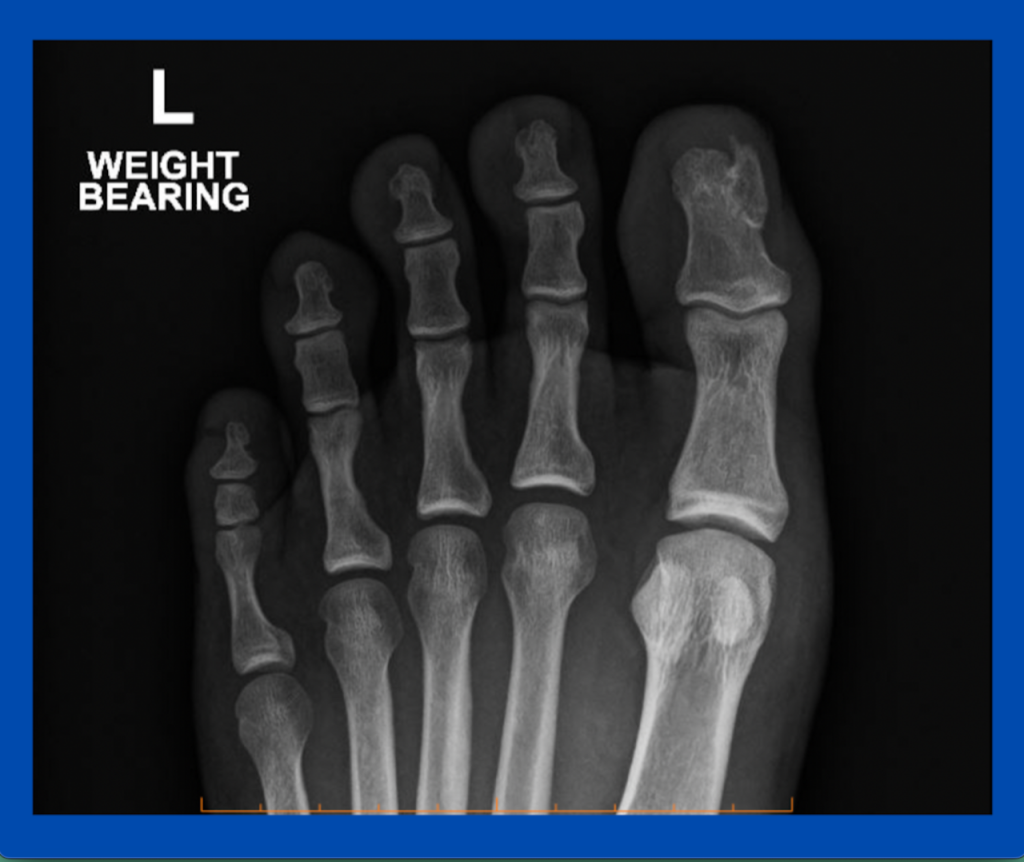

Blog's main page This is one of a few subungual exostoses I see regularly throughout the year. Often when I see these cases, they have been treated as an ingrown toenail for some time. I find they have a very particular appearance (a firm fibrous/callus on top) and sit just under the nail. Sometimes they can [...]

Blog's main page I see a regular amount of subungual exostosis throughout the year. Typically they have been treated as ingrown toenails (IGTN) first. The GP and the podiatrist may assume it is hypergranulation tissue or some other sign of an IGTN and, in some situations, a PNA may have been carried out (not in this [...]